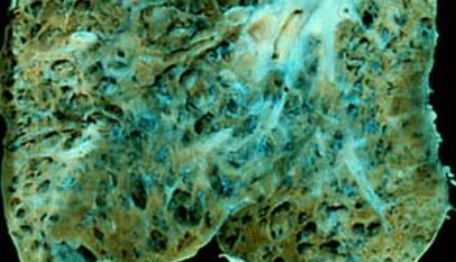

폐섬유증은 폐 조직이 점차 굳어지면서 호흡장애를 일으키는 질환인데요. 폐섬유화증은 폐섬유증의 한 종류로, 폐 조직이 딱딱해지는 현상을 의미합니다. 이러한 변화는 폐에 염증이 생겼다가 아무는 것이 반복되면서 마치 상처가 굳은살과 흉터를 만드는 것과 비슷한데요.

폐섬유증과 폐섬유화증의 주요 원인은 다양합니다. 그러나 가장 흔한 원인 중 하나는 만성 염증입니다. 만성 염증은 폐 조직에 지속적인 염증 반응을 유발하며, 이는 폐 조직의 손상과 염증 반응이 반복되면서 섬유화 과정을 유발합니다. 이 과정에서 폐 조직 내 결합조직이 비정상적으로 증식하고 딱딱하게 굳어지는 현상이 나타나게 됩니다.